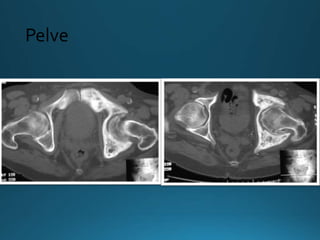

•Pelve:

• Espessamento cortical

• Esclerose das linhas ílio-pectínea e ísquio-púbica

• Asa do ilíaco pode estar envolvida

• Assimétrico (Direita)

• Aumento do ramo púbico e ísquio

Imagem - Rx

Fase mista

Pelve

•Pelve: • Espessamento cortical •Esclerose das linhas ílio-pectínea e ísquio-púbica • Asa do ilíaco pode estar envolvida • Assimétrico (Direita) • Aumento do ramo púbico e ísquio Imagem - Rx Fase mista